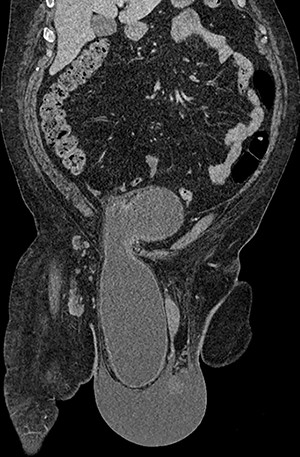

Computed tomography (CT) scan of the abdomen and pelvis with contrast revealed a large right indirect inguinal hernia containing a significant portion of the bladder within the scrotum (Figs 1–3). There was associated bilateral hydronephrosis and hydroureter, and significant scrotal oedema seen within the soft tissues.

Sagittal CT image of the abdomen and pelvis demonstrating herniation of the bladder into the scrotum.